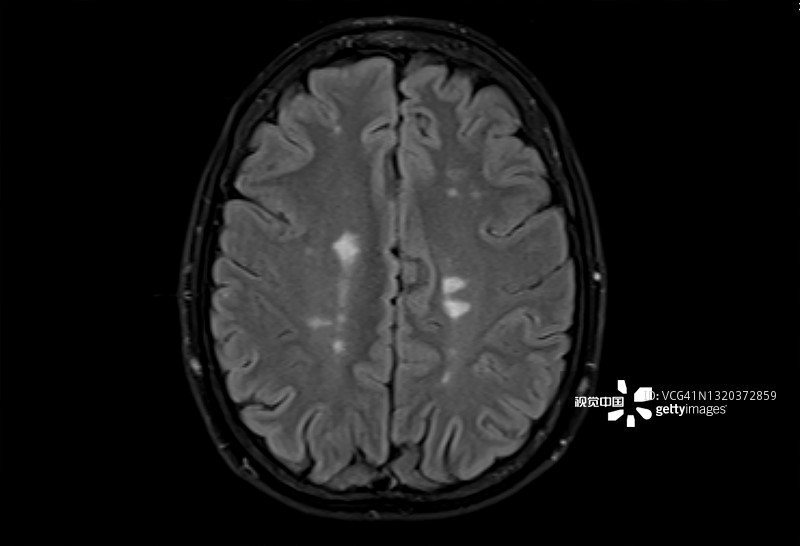

多發(fā)性硬化癥 (MS):MS是一種中樞神經(jīng)系統(tǒng) (CNS) 的慢性自身免疫和炎癥性疾病。MS與免疫系統(tǒng)介導的自身反應性T細胞和B細胞對神經(jīng)元髓鞘的攻擊有關,導致脫髓鞘并最終導致神經(jīng)元丟失。由于中樞神經(jīng)系統(tǒng)中神經(jīng)變性和斑塊的形成,MS患者會根據(jù)斑塊的位置經(jīng)歷特定的神經(jīng)功能障礙。例如,視神經(jīng)中的斑塊會導致視力喪失。